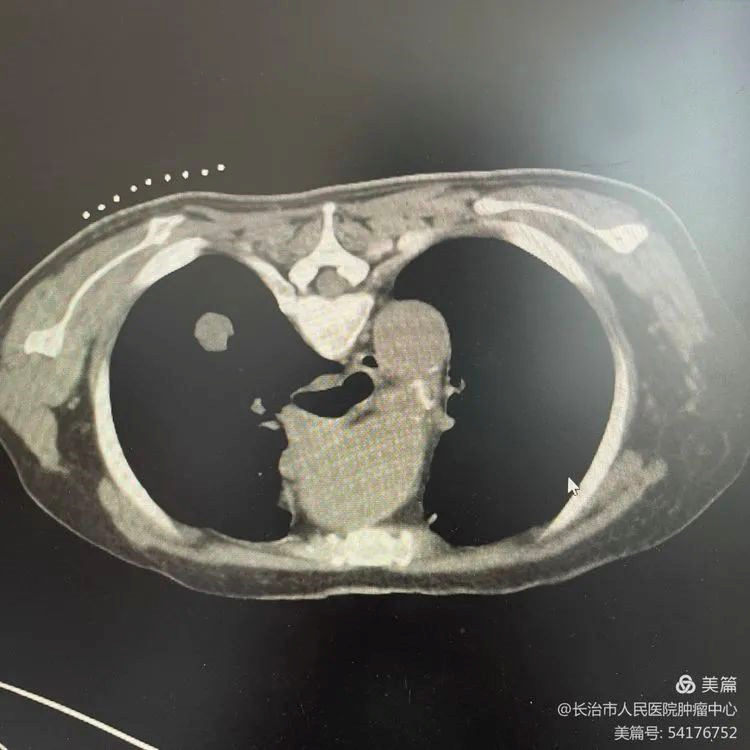

第一步:CT下病灶定位,确定穿刺点

image.png